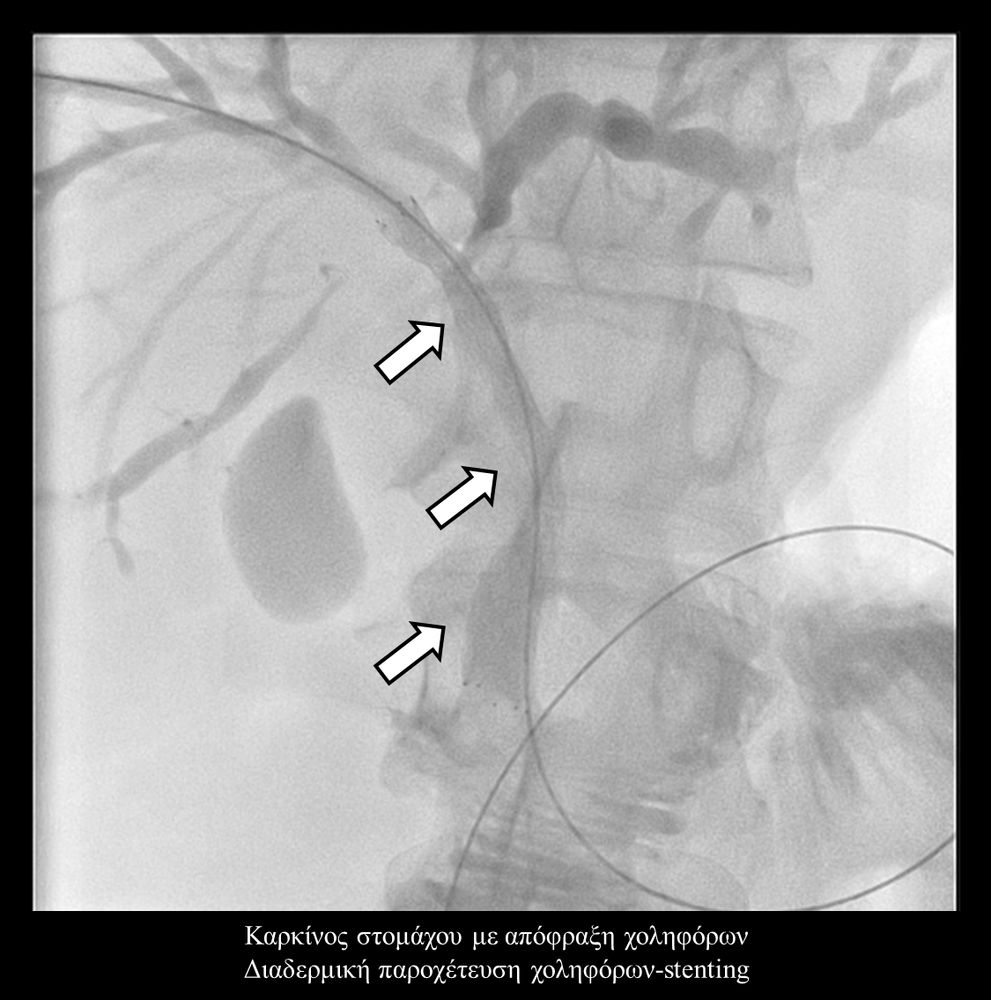

Σε πολλές περιπτώσεις πρωτοπαθών ή δευτεροπαθών όγκων ήπατος - παγκρέατος προκαλείται απόφραξη των χολαγγείων με συνοδό αποφρακτικό ίκτερο.Ο ασθενής με αποφρακτικό ίκτερο δεν μπορεί να υποβληθεί σε χημειοθεραπεία, αν δεν αποκατασταθεί ο ίκτερος με παροχέτευση των χοληφόρων.

Σε περιπτώσεις όπου υπάρχει απόφραξη των χοληφόρων και ενδείκνυται η τοποθέτηση ενδοπρόθεσης (stent), τότε η βατότητα των χολαγγείων και η αντιμετώπιση του αποφρακτικού ικτέρου μπορεί να διασφαλιστεί με την τοποθέτηση ενδοπροθέσεων (stents).

Η προσπέλαση σε όλες τις περιπτώσεις γίνεται διαδερμικά και η νοσηλεία του ασθενούς διαρκεί συνήθως μία ημέρα και ο ασθενής επιστρέφει στο σπίτι του την επομένη.